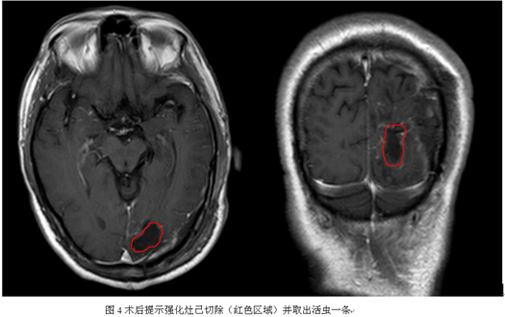

手术过程顺利,抓获脑裂头蚴活虫一只,长约11厘米。术后患者无明显功能障碍,目前已康复出院。

治疗:本病的治疗关键是去除活的虫体,因此,手术常为首选方法。由于裂头蚴可在颅内活动,往往造成多发病变,给确定活虫位置造成一定困难,特别是当病变累及重要功能区时,往往使得手术抓获活虫体难度增加。我们的经验是:重视患者癫痫发作症状学演变和最近的影像学变化,往往新的病变区域或新的症状产生代表区域是活虫所在区域。而且神经导航指引下手术是必需的。资料显示,一般只要去除完整的虫体,病人的临床症状即可得到明显的缓解或痊愈,一般无需特殊药物治疗。